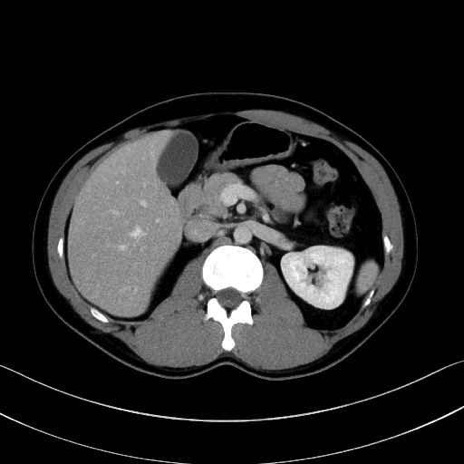

【症例】20歳代 男性 スクリーニング

■起始:典型的には腹腔動脈幹(celiac trunk)から左胃動脈・総肝動脈とともに三分岐し、脾動脈は左後上方へ向かう。

■走行:膵上縁または膵実質背側を蛇行しながら左方へ進み、膵尾部近傍で脾門へ至る。蛇行の程度は個体差が大きい。

■終枝:脾門部で複数の終末枝に分かれ、上極・下極枝や脾門枝群を形成する。胃短動脈群や左胃大網動脈はしばしば脾動脈から分岐する。